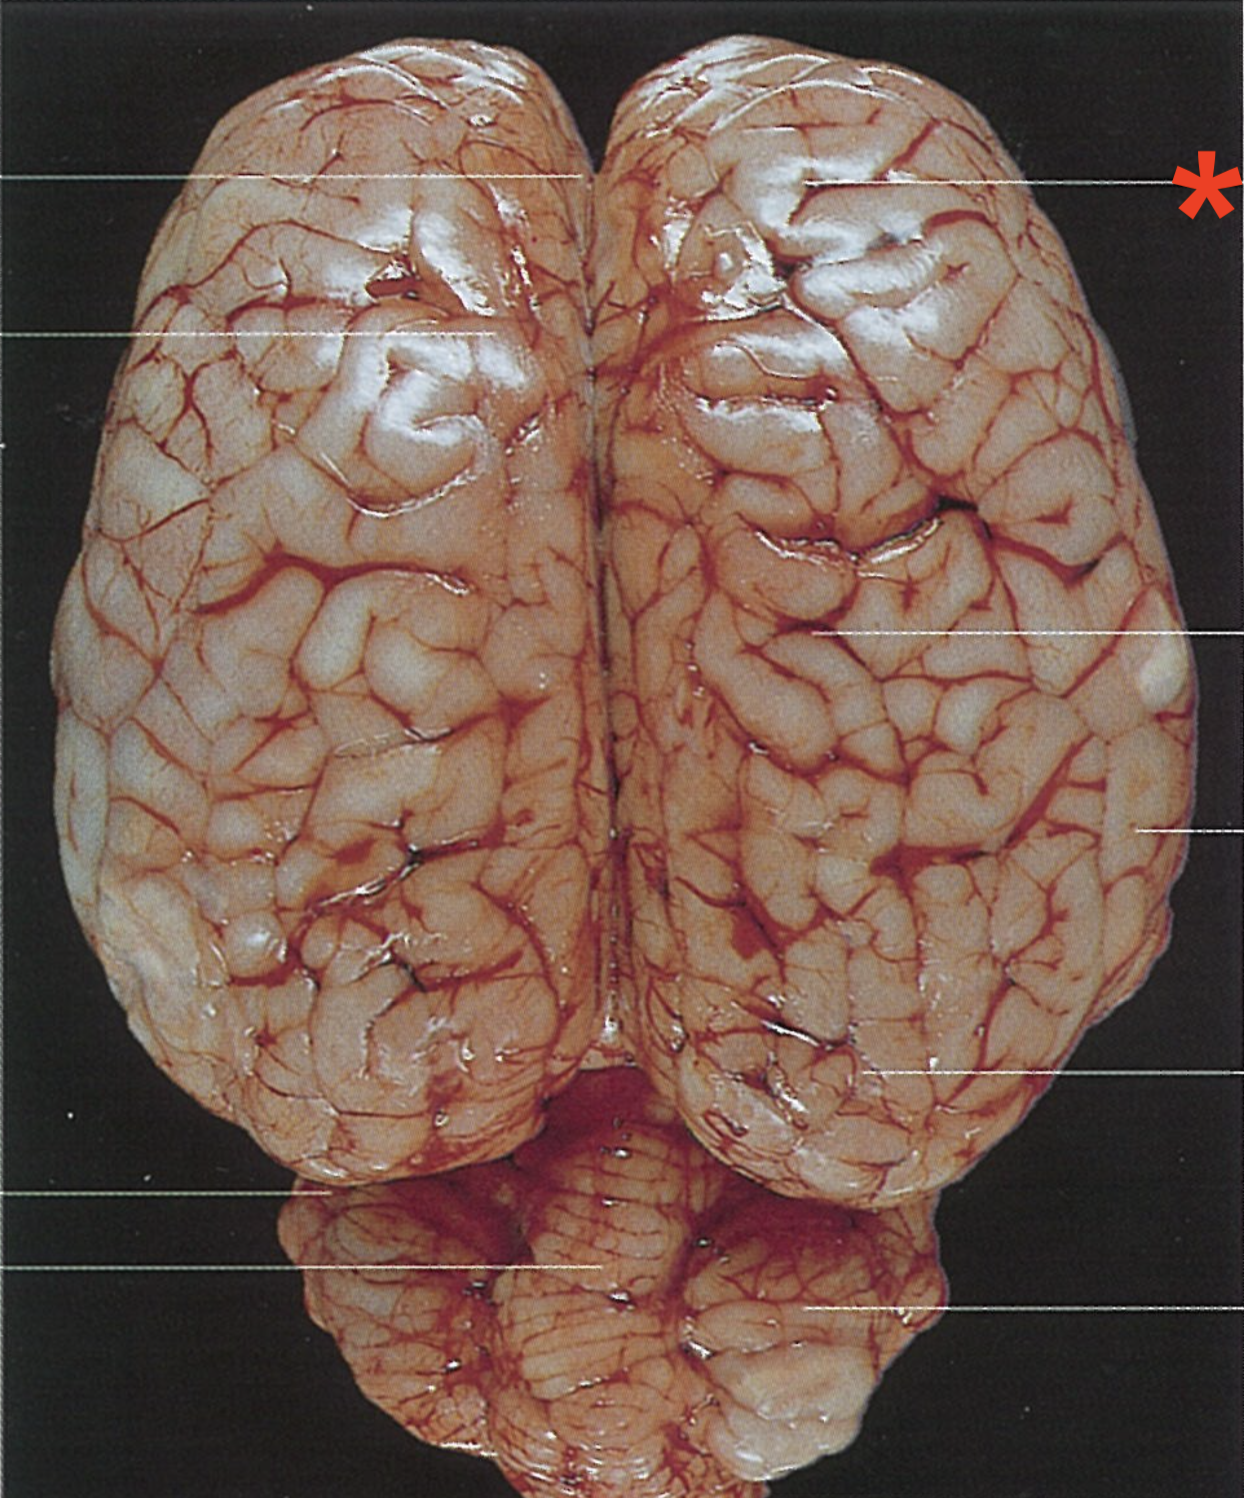

What is the telencephalon composed of?

Paired cerebral hemispheres

Longitudinal cerebral fissure

Frontal lobe

Cruciate fissure

Parietal lobe

Temporal lobe

Occipital lobe

What separates the two hemispheres of the telencephalon

Cerebral longitudinal fissure

What are the elevated bands found on the surface of the telencephalon hemispheres?

Gyri cerebri

What separates the gyri cerebri?

Sulci cerebri